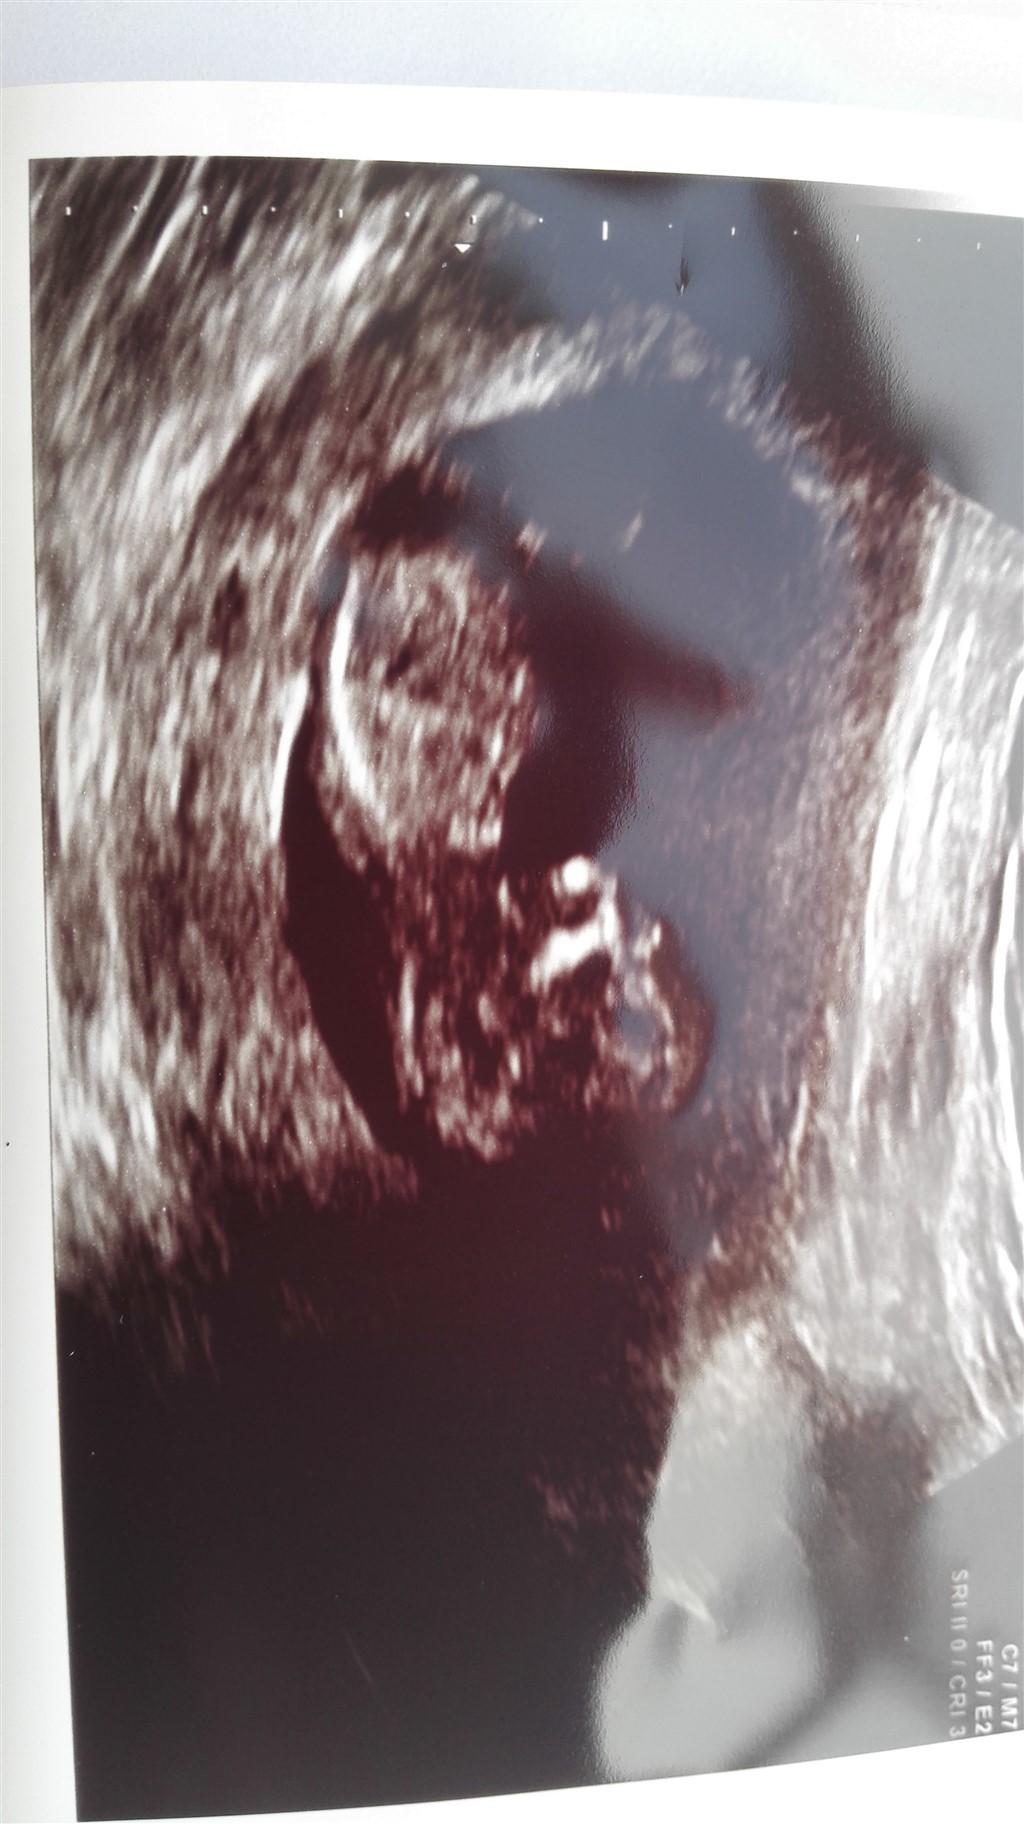

Men men idag har jeg været til scanning og der er en fin lille my og er i 12 uge med termin den 22-3

Vedhæftede fotos (klik for at se i fuld størrelse)